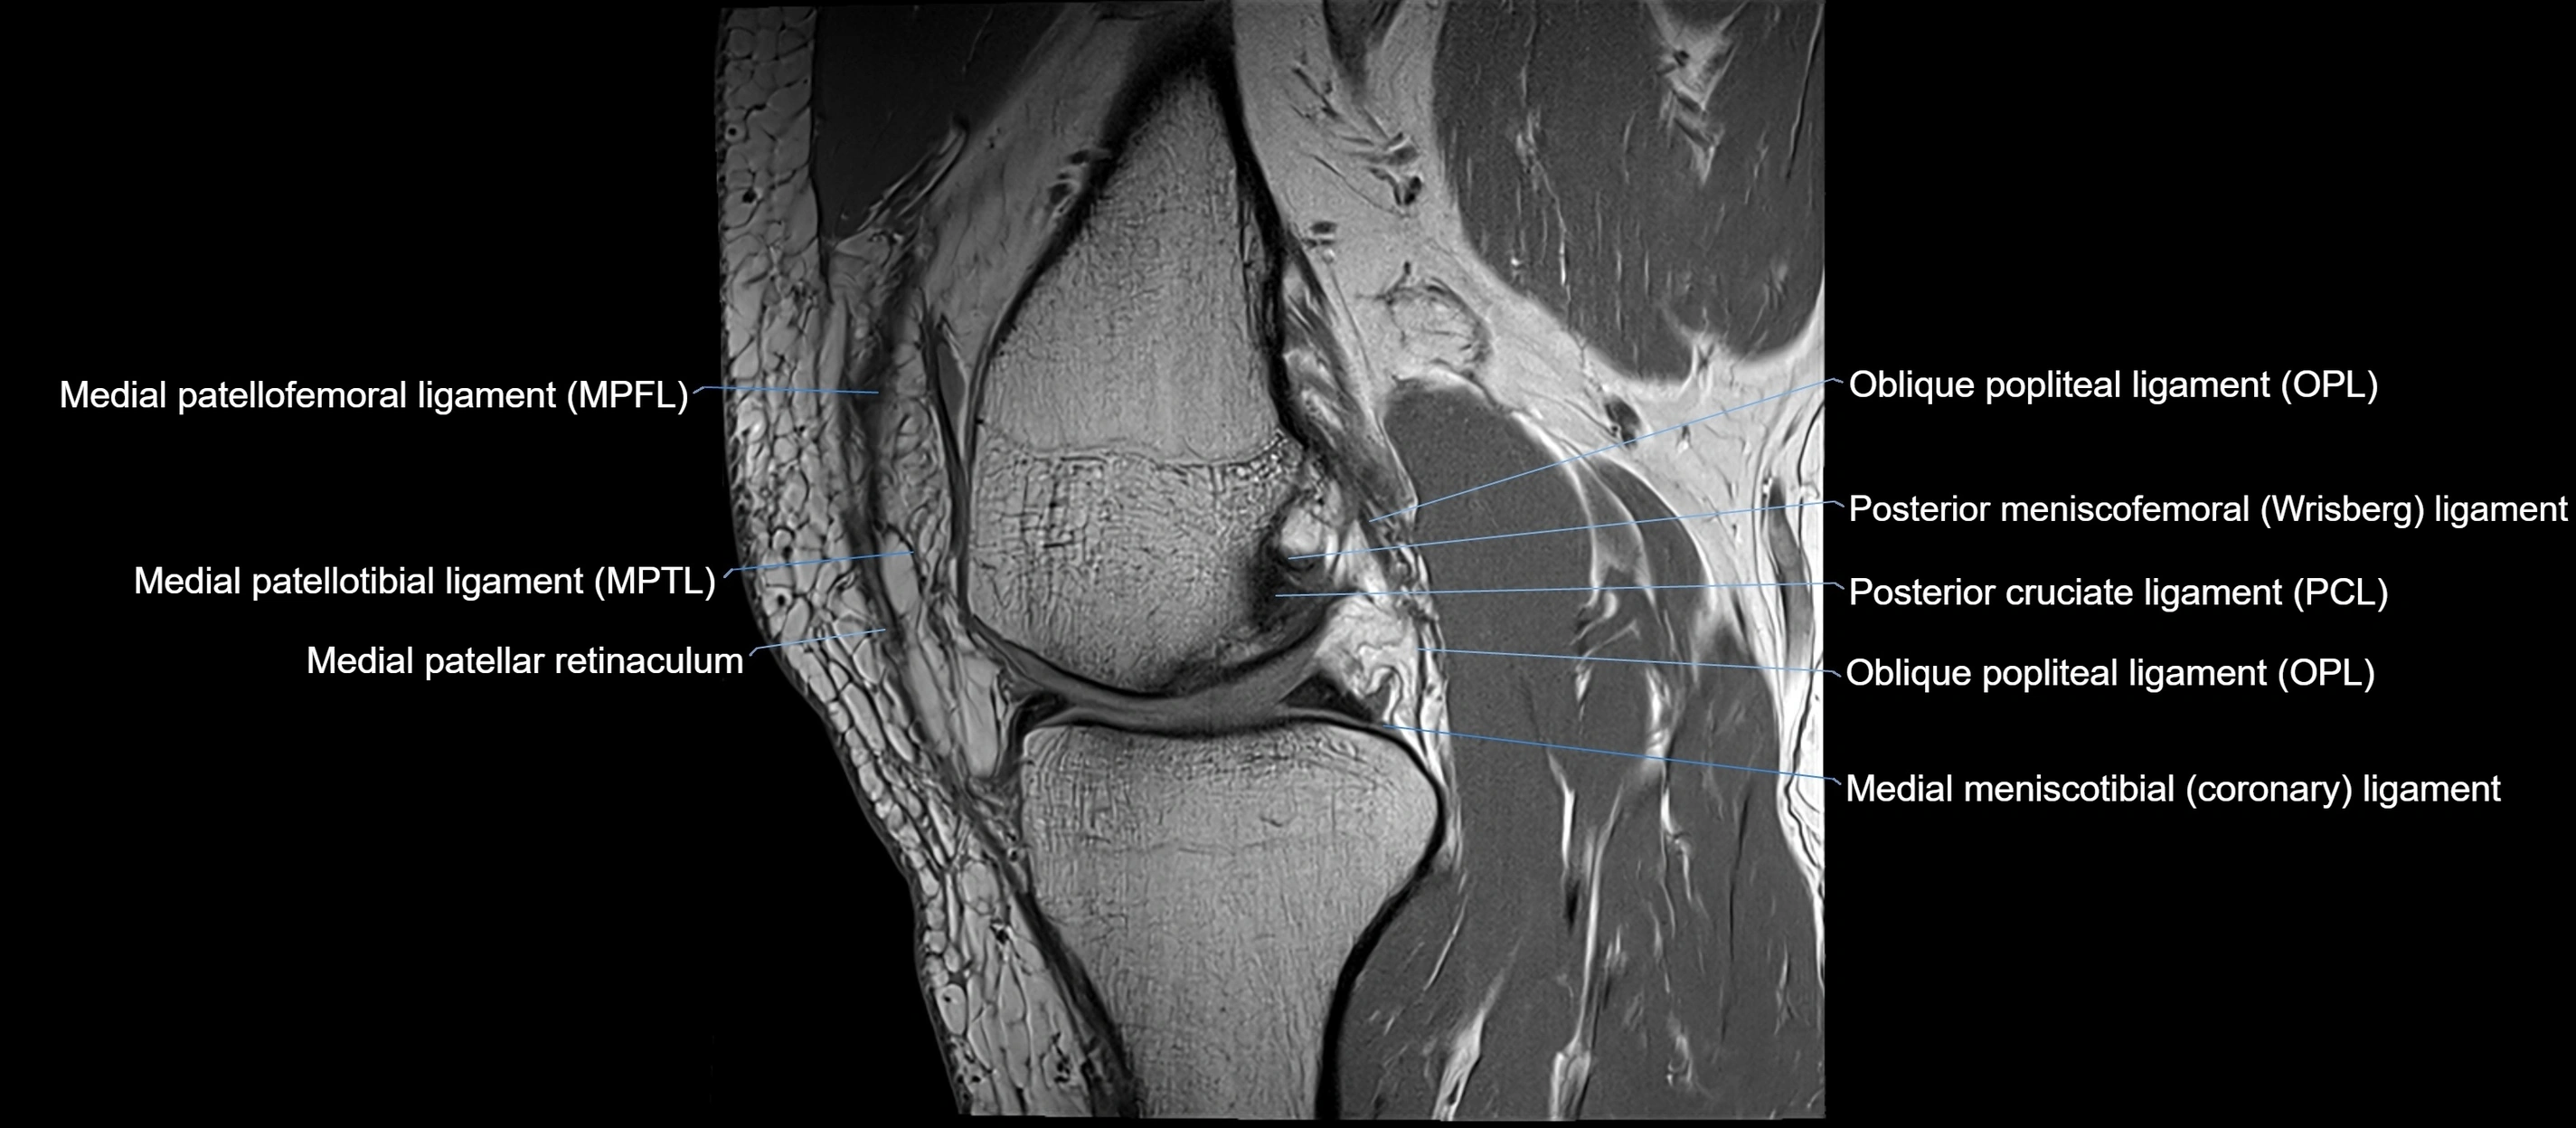

MRI images

image

MRI Appearance

T1-weighted images:

• Normal ACL appears as a low-signal band-like structure crossing the intercondylar notch

• Surrounded by intermediate signal synovial fluid and fat planes

T2-weighted images:

• Normal ACL remains low signal

• Partial or complete tears appear as discontinuity, increased signal, or fiber laxity